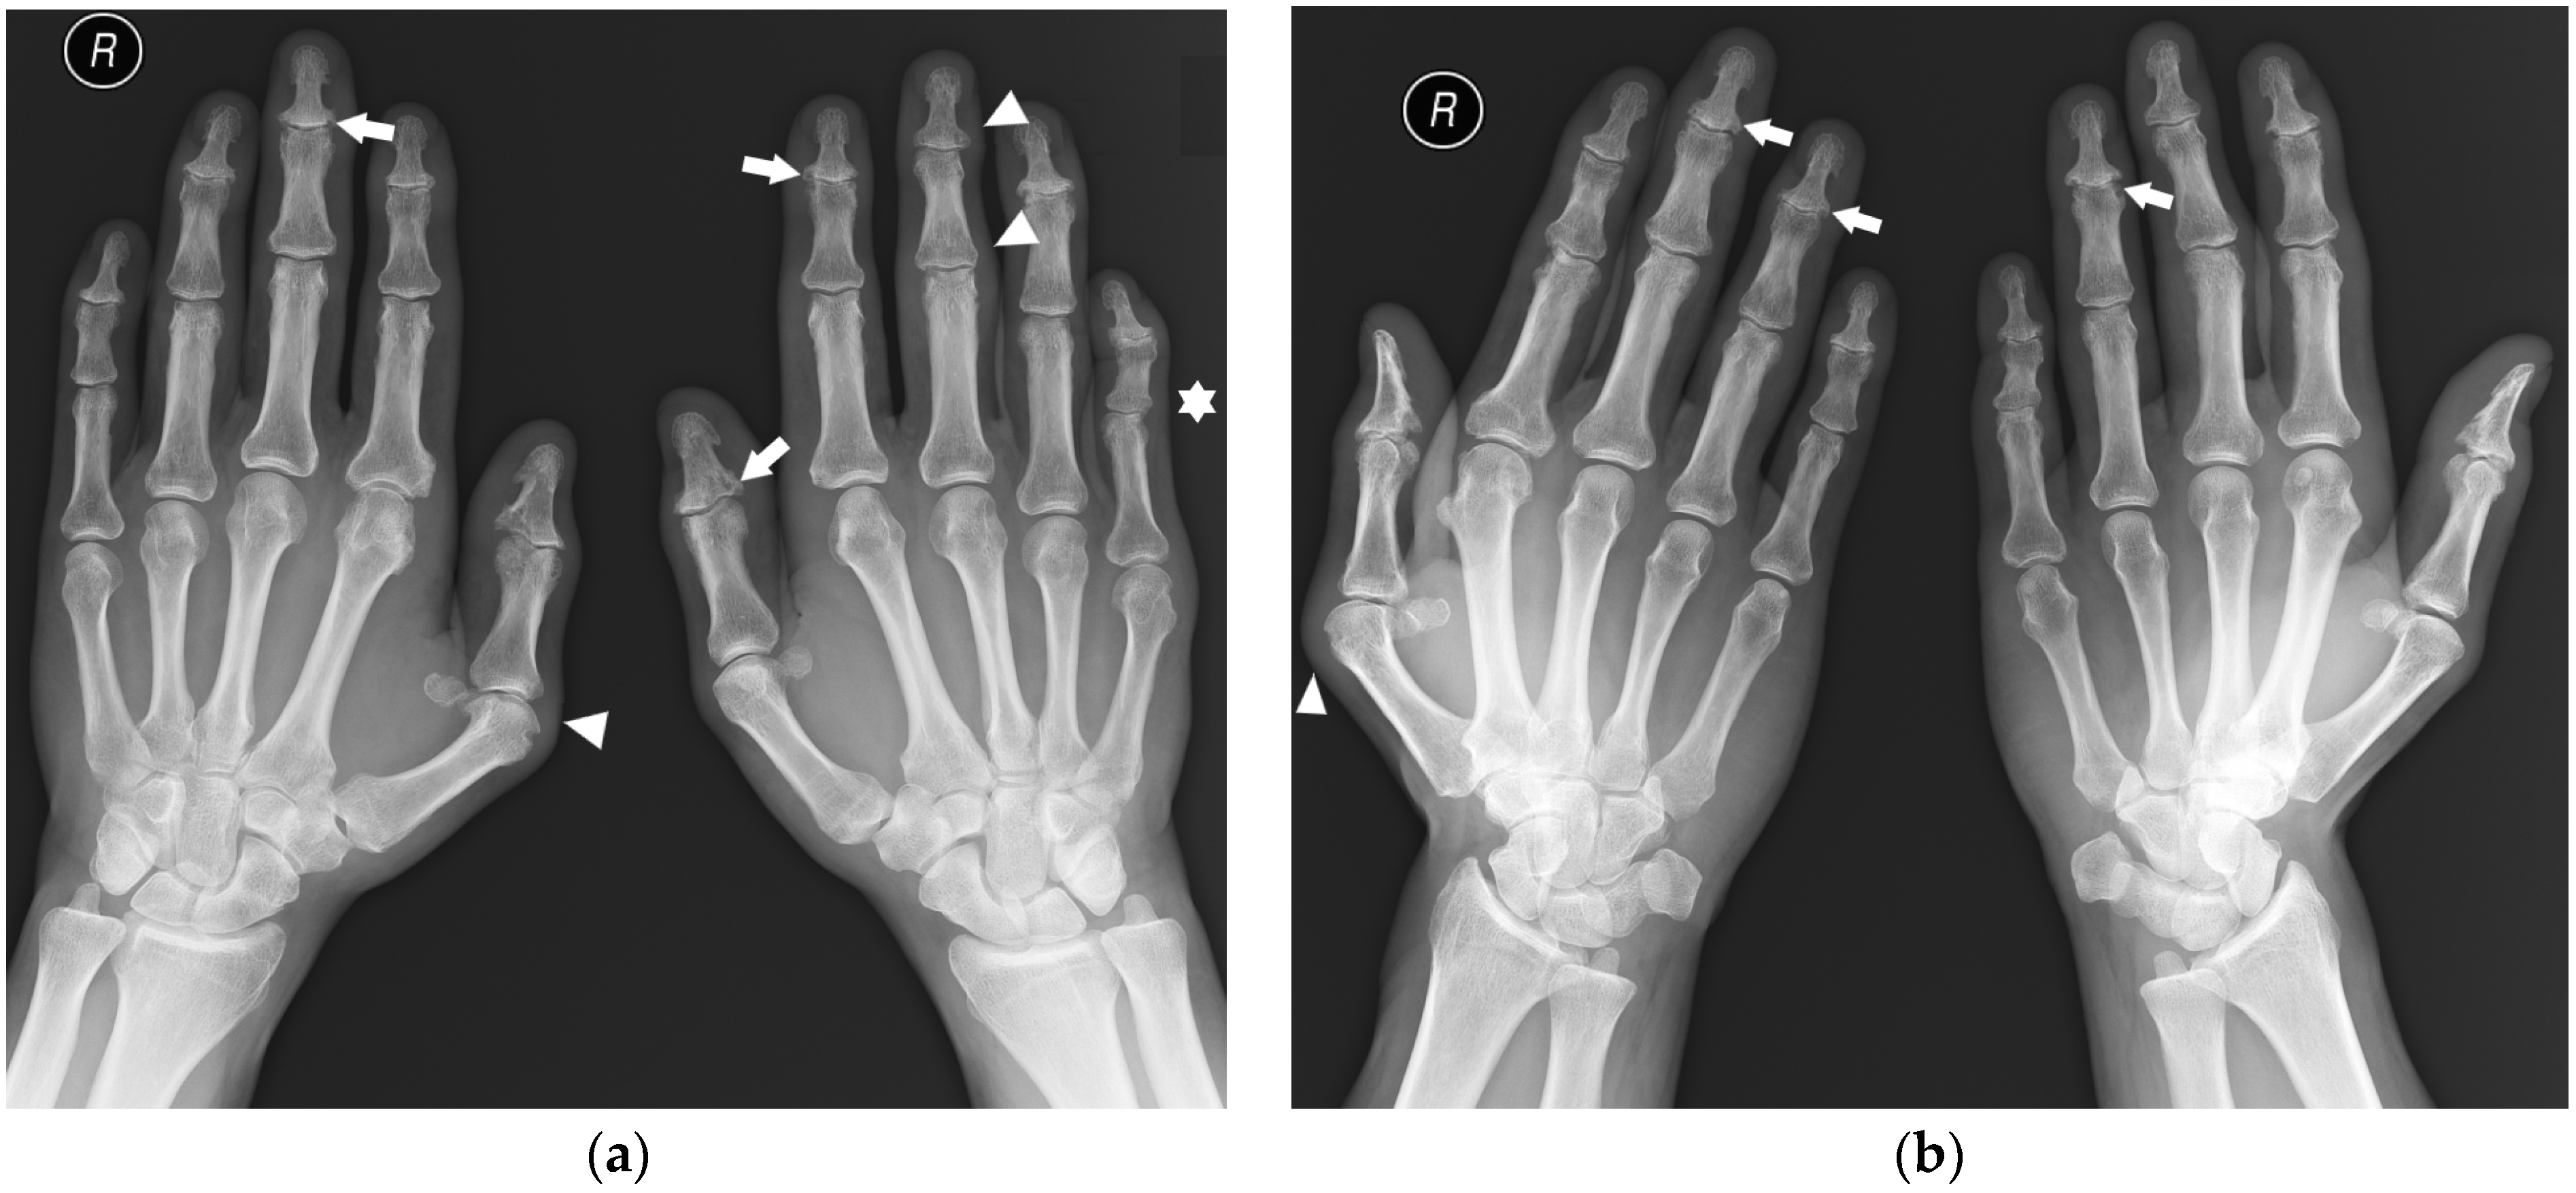

Erosions, bone cysts, and malalignments can be present in both PsA and RA. The hallmarks distinguishing hand and foot radiographs of PsA from RA are proliferative bone changes in combination with erosions, predilection to DIP joints, acroosteolysis (although rarely seen), lack of juxta-articular osteoporosis, and asymmetric distribution with the involvement of a single ray or several rays with dactylitis [1,6] (Figure 2). Advanced changes can form pencil-in-cup deformities [21].

Figure 2.

A 45-year-old male with psoriatic arthritis (PsA). PA (a) and Nørgaard views (b) of bilateral hands. Note the swan neck deformities, most prominent in the left small finger (star). There is soft tissue swelling around several distal interphalangeal (DIP) and thumb interphalangeal (IP) joints, as well as the right first MCP and left third proximal interphalangeal (PIP) joints (arrowheads). Note the scattered bone cysts, erosions, and proliferative bone changes at several DIP joints and the left thumb IP joint (arrows). There are erosions in the right first metacarpal (MC) head and a bone cyst and small erosion in right second MC head.